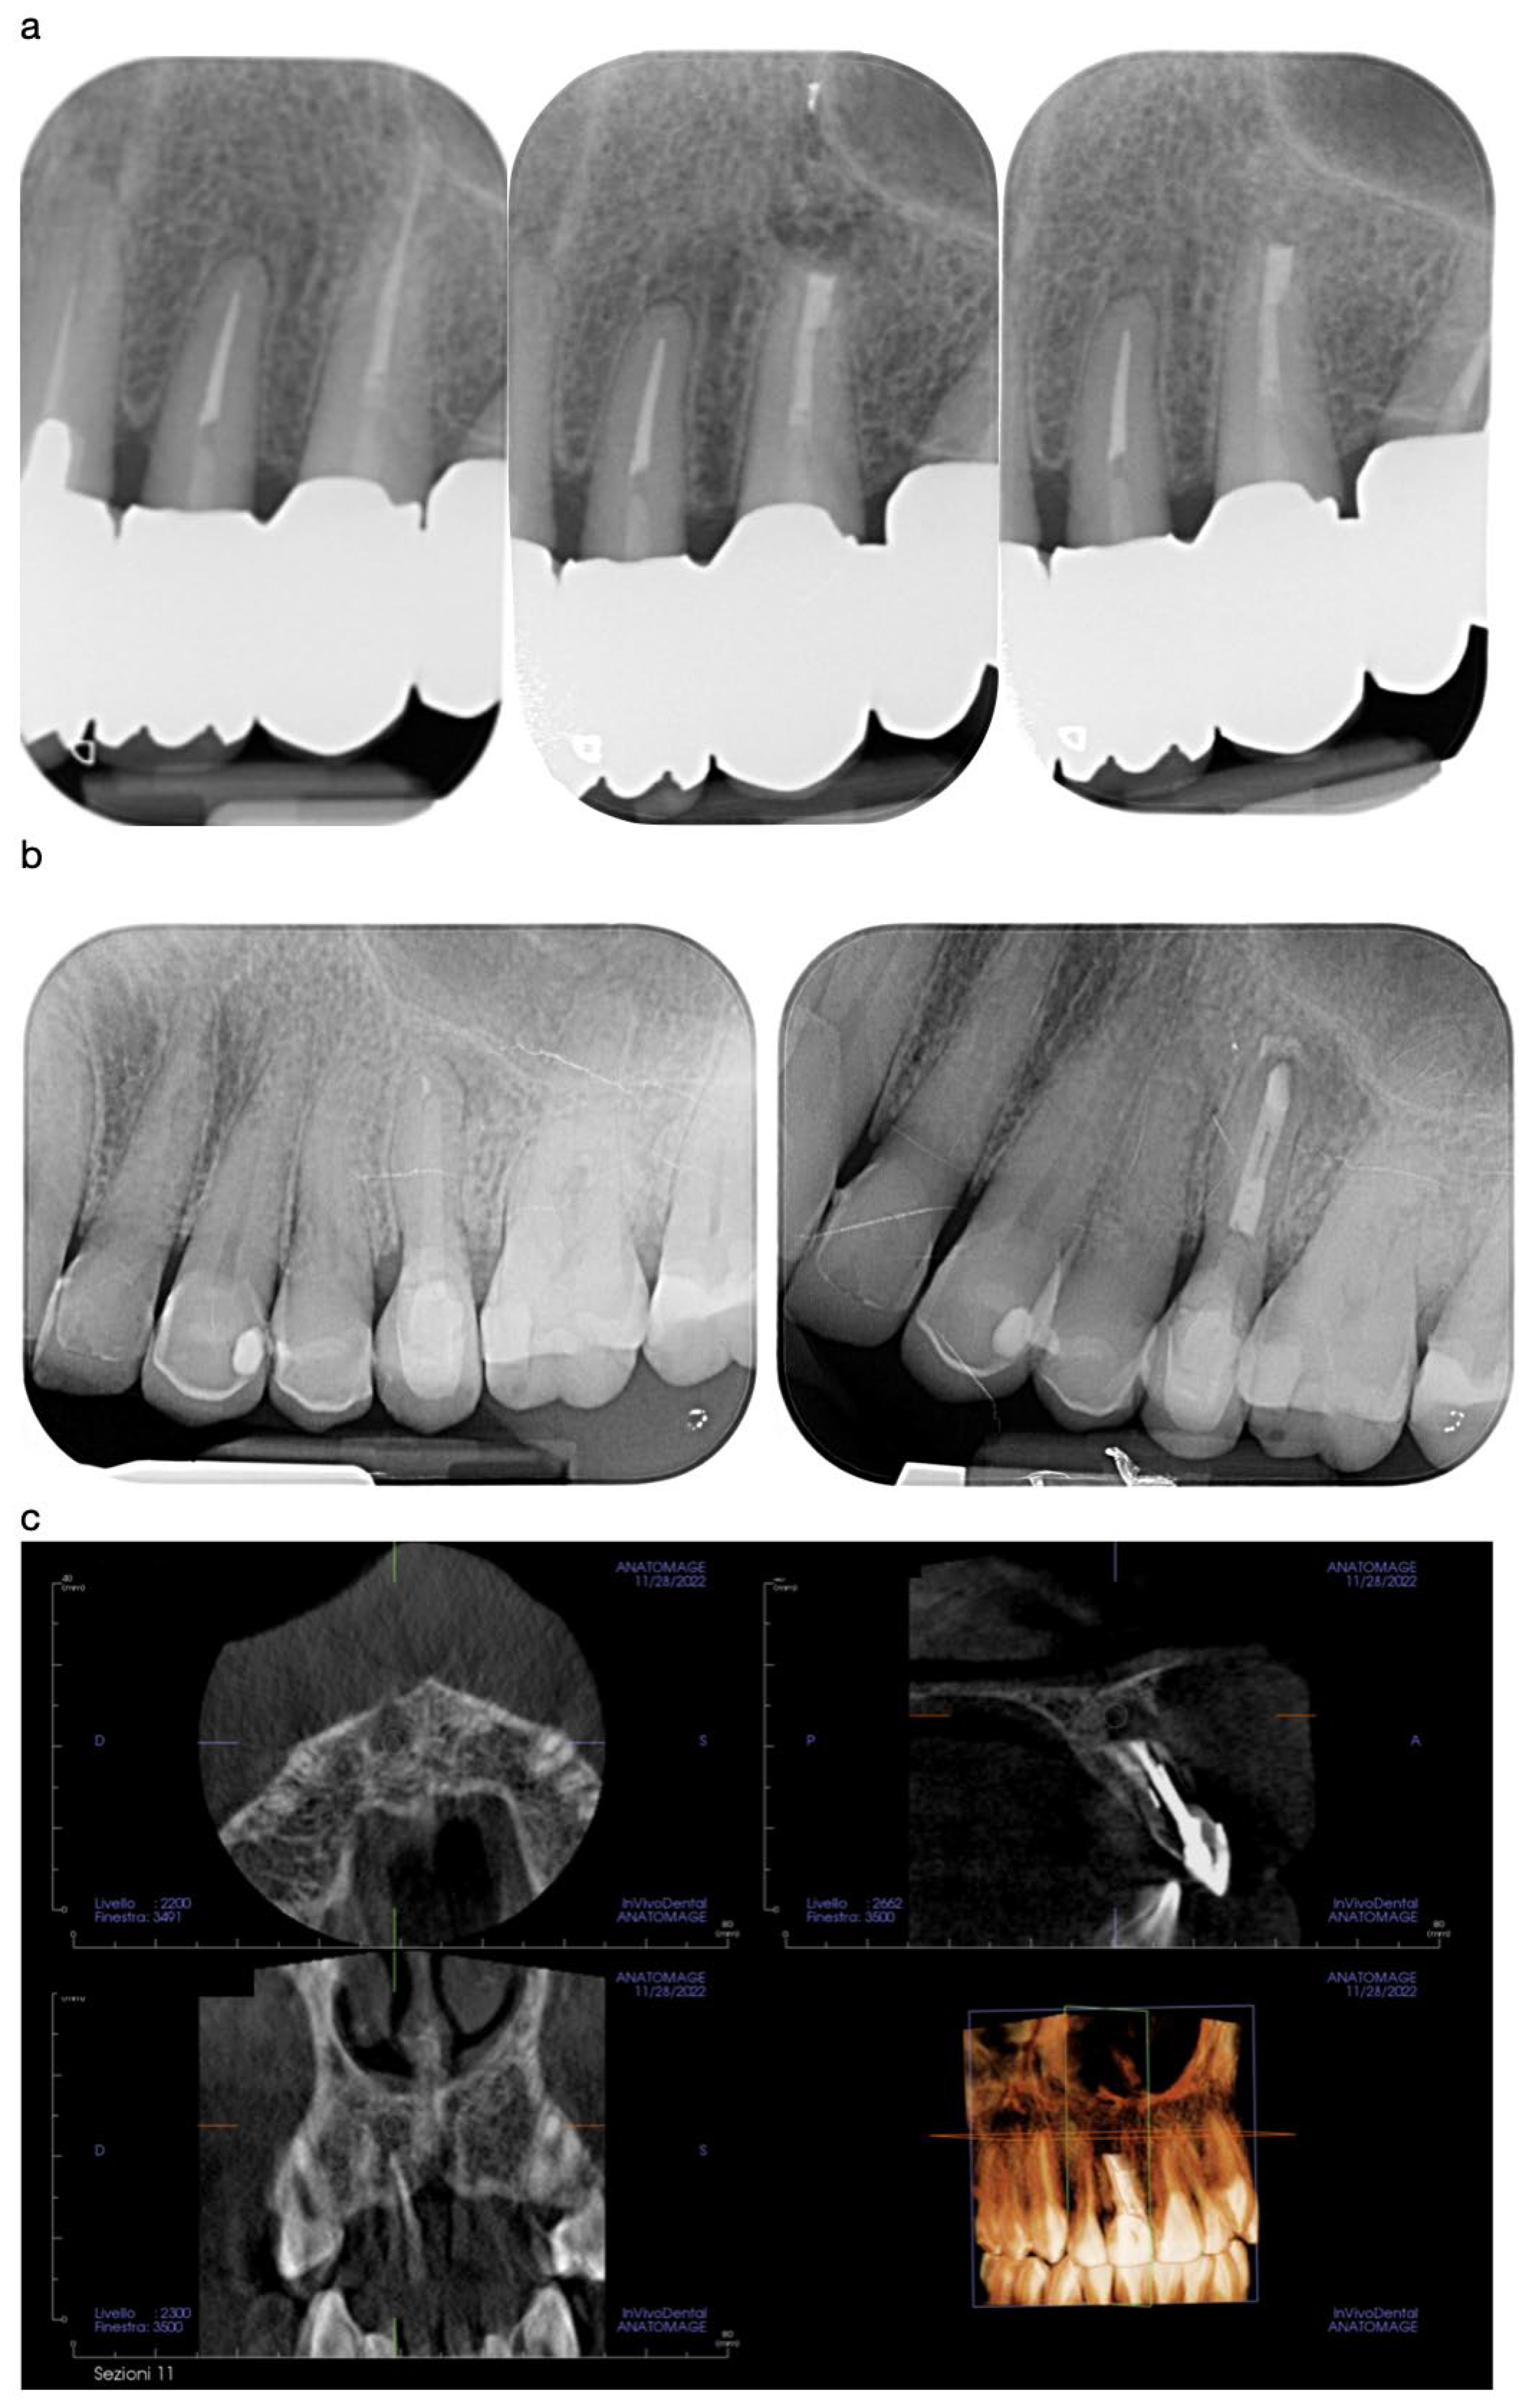

Healing: Follow-up radiographs/CBCT scans were taken at 6 weeks (T1) and at 6 months (T2) to evaluate periapical healing. Lesion size (mm) and presence of radiopaque healing were recorded.

Postoperative pain decreased markedly in all patients from a mean VAS score [4 ± 2] at T0 to [1 ± 1] at T2. Radiographic examinations revealed progressive healing of the periapical areas, with a clear reduction in lesion size in all cases [Figure 6]. None of the patients reported persistent swelling or adverse effects. A summary of the main findings is presented in [Table 1], including individual case data on apex resection length, final retrograde filling, and healing status at T2.

Figure 6. Radiographic follow-up showing good bone remodelling in the periapical region T0; T1; T2 (a) and T0; T2 (b), and postoperative CBCT showing effective removal of the cystic lesion of the 11 (c) at T1.